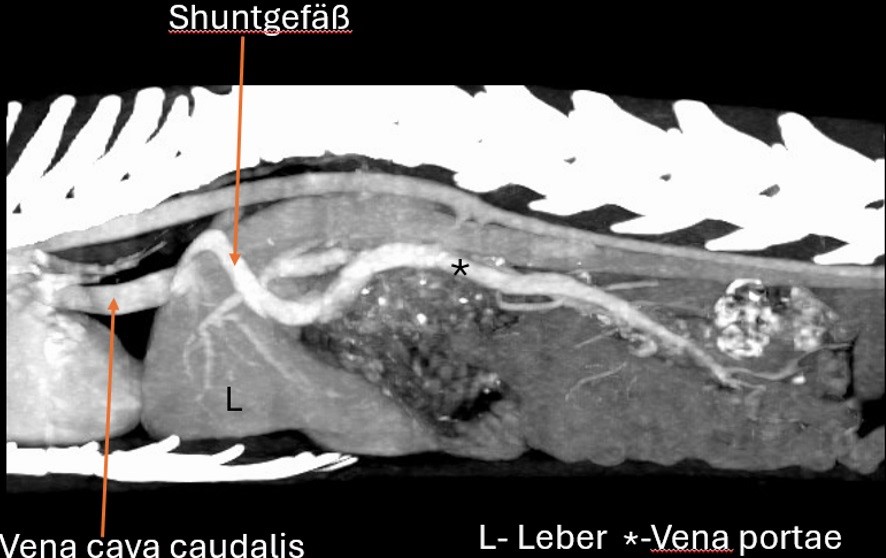

Eine vollständige Ultraschalluntersuchung war aufgrund mangelnder Kooperation des Patienten nicht möglich, daher wurde entschieden, den Kater initial zu stabilisieren und später eine Abdomen-CT in Narkose durchzuführen. Petzi wurde stationär aufgenommen und symptomatisch mit Dauertropfinfusion und Maropitant 1 mg/kg i.v. behandelt. Am nächsten Tag wurde in Narkose eine CT-Angiographie (jodhaltiges Kontrastmittel 2 ml/kg) durchgeführt. Die Narkoseeinleitung erfolgte mit Midazolam 1 mg/kg, Ketamin 20 mg/kg und anschließend Propofol 2-5 mg/kg nach Wirkung; die Narkose wurde mit Sevofluran 2,5 % erhalten. Ein extrahepatischer portosystemischer Shunt (PSS) in Form eines linken Gastrophrenica-Shunts konnte dargestellt werden (Abb. 3, 4). Aufgrund des Schweregrades der Symptomatik wurde entschieden, den extrahepatischen PSS auf dem chirurgischen Weg noch in derselben Woche zu versorgen.